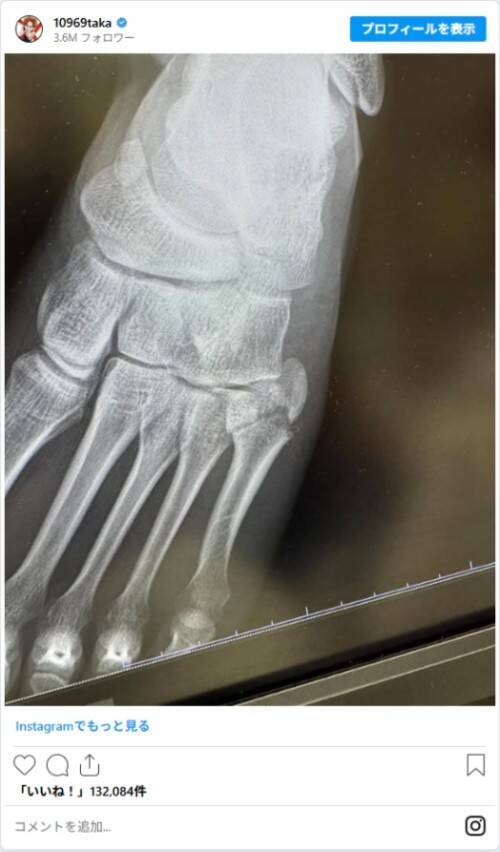

メッセージ動画とレントゲン写真を投稿し、ライブ中に左足を骨折したことを報告しました。

動画では「人生初、公演中に足を骨折しました」と明かし、歌唱中に足を着いた際に左足小指の付け根を痛めたと説明。「ものすごい勢いでぐちゃってなった」とその時の状況を語っていました。

Instagramには、「ポッキリ」と言葉を添えてレントゲンも公開。